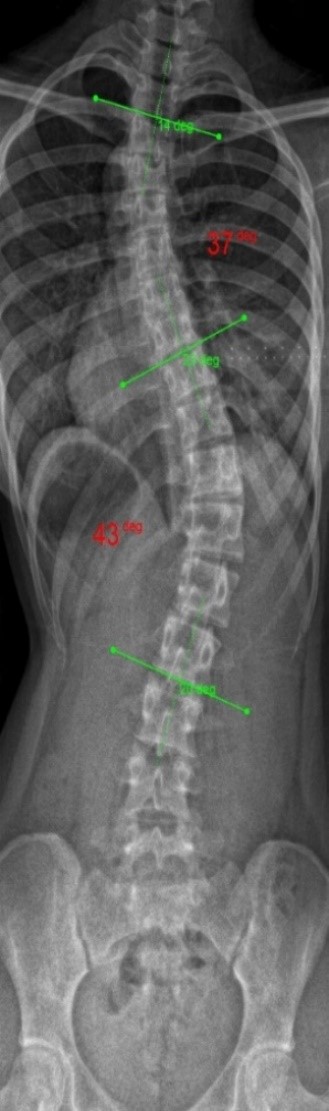

The clinical test results show that the SCN800 series is highly consistent with the X-ray, with a linear correlation of 0.94, similar results have also been published in SCI articles (Lee TT, Lai KK, Cheng JC, Castelein RM, Lam TP, Zheng YP. 3D ultrasound imaging provides reliable angle measurement with validity comparable to X-ray in patients with adolescent idiopathic scoliosis. Journal of Orthopaedic Translation. 29:51-59, 2021).

In our clinical trials and studies, we measured two angles to facilitate comparison. X-rays can actually show 3 to 4 angles, some in the neck and bottom area. Ultrasound images can also measure angles near the neck like an X-ray.

The following images compare 5 ultrasound and X-ray clinical measurement examples: